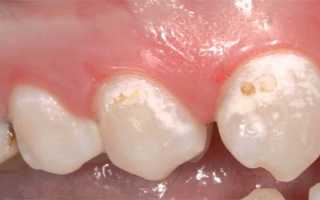

При кариесе сначала появляются белые пятна. Лечение может проводиться без применения бормашины с помощью реминерализации и фторирования. При поражении эмали она становится мягкой и шершавой, и если не начать лечение, пятна становятся темнее и проникают вглубь, переходя в следующую стадию кариеса. Часто пятна образуются на пришеечной и боковой поверхностях.

Гипоплазия — это врожденный дефект, который может вызываться проблемами в период эмбрионального развития. Это состояние может быть обусловлено токсикозами во время беременности матери, а также родовыми травмами и инфекциями. Если у ребенка появляется белое пятно на зубе, причиной может быть нарушение обменных процессов или недоразвитие. В молочном периоде пятна обычно появляются на передних зубах ребенка. Имея гипоплазию, зубы становятся уязвимыми, поэтому требуются защитные процедуры с использованием специальных средств. Стоматолог может определить возраст нарушения эмали по месту положения пятен.

Белые оттенки на зубах ребенка могут иметь желтоватый или коричневатый цвет. Они могут появляться из-за различных факторов, таких как развитие кариеса, недостаточная гигиена полости рта, гипоплазия, употребление кислотной пищи, системные заболевания, травмы зубов, насыщение организма фтором и различные отклонения в развитии ребенка. Гипоплазия может проявляться в виде полос, затемнений или поражений одного или нескольких зубов. Ортодонтическое лечение также может быть причиной поражений, когда скобы предотвращают контакт зубной части с слюной, что препятствует минерализации. Важно обратиться к стоматологу, чтобы установить причину и своевременно устранить проблему. Молочные зубы с белыми пятнами также следует сохранить до появления постоянных зубов. Диагноз может быть сложным, но опытный стоматолог может определить время протекания патологии и факторы раздражения. Также важно уделить внимание иммунной системе ребенка. Появление белых пятен после инфекционных заболеваний, перенесенных зимой, наблюдается у многих детей. Поэтому рекомендуется проводить закаливающие процедуры, заниматься спортом и проводить время на свежем воздухе. Стоматолог учитывает информацию о болезнях матери во время беременности при диагностировании белых пятен на молочных зубах ребенка.